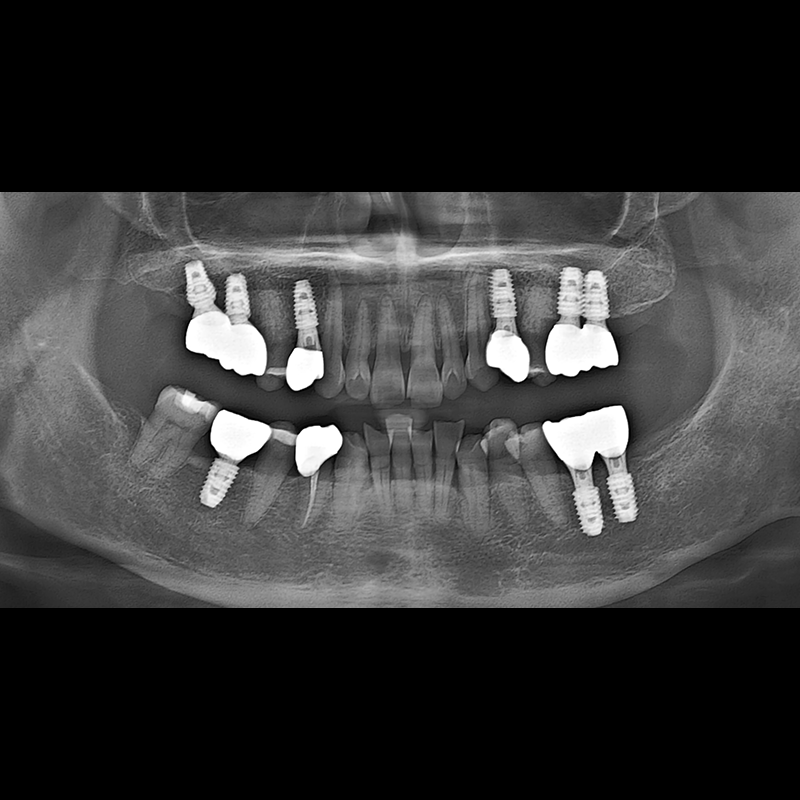

BEFORE AFTER

Implant before and after 2025.05.30

Implants were placed in the missing tooth and in the tooth position where it was difficult to save.